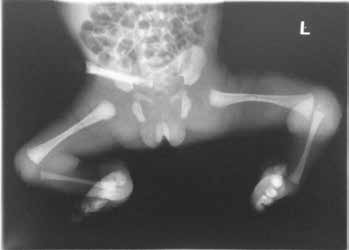

Pränatal wird bei der Patientin im Ultraschall eine beidseitige Fehlbildung der unteren Extremität diagnostiziert. Die Patientin kommt per Sectio in der 31. SSW als Frühgeborenes (Abb. 4a) zur Welt. Das Krankheitsbild präsentiert sich nach der Geburt als beidseitige Tibiaaplasie, rechts Grad 1, links Grad 2a (Abb. 4b). Rechtsseitig besteht eine Kniebeugekontraktur von 110°. Die Patellaaplasie zieht einen fehlenden Muskelstreckapparat nach sich, der Fuß steht in Inversion und Klumpfußstellung, die Großzehe ist hypoplastisch. Linksseitig ist das Kniegelenk frei beweglich. Patella und Streckapparat sind vorhanden, ein Tibiaplateau ist erkennund tastbar. Der linke Fuß steht ebenfalls in Inversions- und Klumpfußstellung. Ein Herzfehler und das sehr niedrige Geburtsgewicht machen zunächst einen mehrwöchigen stationären Aufenthalt notwendig.

Behandlungsverlauf (Abb. 5a–e)

- Ab Mai 2009 beginnen die orthopädische Behandlung der Beugekontraktur des rechten Kniegelenkes mit redressierenden Gipsen sowie das konservative Redressment beider Füße.

- Im Oktober 2009 erfolgt die Erstvorstellung im Universitätsklinikum Münster, im März 2010 die operative Distraktion, Redression und Rekonstruktion der Deformitäten mit externen Fixateuren (Abb. 5a). Die Fixateure werden über ein halbes Jahr in zwei Phasen à drei Monaten mit täglichem Redressment angepasst.

- Der rechte Fixateur distrahiert und fixiert Oberschenkel, Unterschenkel und Fuß. Linksseitig wird nur der Unterschenkel zum Fuß in Stellung gebracht.

- Im Oktober 2010 erfolgt eine operative Unterstellung mit Kirschnerdrähten am linken US und Fuß, am rechten OS und US und am rechten US und Fuß. Anschließend findet ein 10-wöchiges Gipsredressment statt.